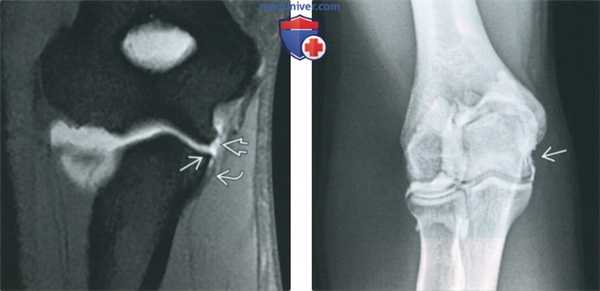

(Слева) Рисунок, латеральная поверхность локтевого сустава: показан разрыв переднею пучка локтевой коллатеральной связки (ЛоКС). Задний и поперечный пучки не изменены. Характерным для разрыва ЛоКС является повреждение переднею пучка, но может наблюдаться повреждение еще и заднего пучка.

(Справа) МР-артрография в режиме Т2ВИ FS, коронарный срез: отмечается отрыв переднею пучка ЛоКС с ретракцией культи в дистальном направлении. Также наблюдается поверхностный разрыв сухожилий сгибателей.

(Слева) МР-артрография в режиме Т1ВИ FS, коронарный срез: визуализируется поверхностный разрыв ЛоКС. Связка отделилась от возвышенного бугорка, но дистальнее осталась прикрепленной. Такая картина получила название симптома «Т». Проксимальный отдел связки неравномерно истончен.

(Справа) Артрография, передне-задняя проекция: отмечается неровный контур ЛоКС, соответствующий ее поверхностному разрыву.